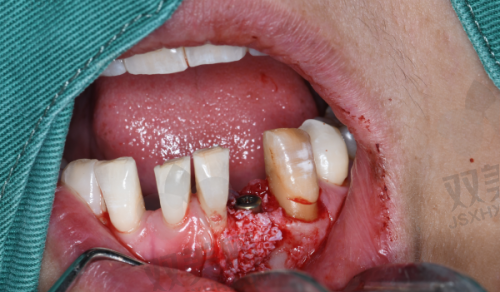

种牙齿手术通常分为几个步骤。首先是术前检查,医生会对患者的口腔进行全方面检查,包括拍摄X光片、CT等,以了解牙槽骨的情况、确定种植体的位置和方向。接着是局部麻醉,在麻醉生效后,医生会在牙槽骨上制备一个合适的种植窝,然后将种植体植入其中。之后会缝合创口,等待种植体与牙槽骨愈合,这个过程一般需要3 - 6个月。待种植体与牙槽骨达到良好的骨结合后,再进行二期手术,安装基台。末尾制作并安装牙冠,整个种牙齿手术就完成了。整个过程中,患者在局部麻醉下通常不会感到明显的疼痛,但术后可能会有一些轻微的不适。